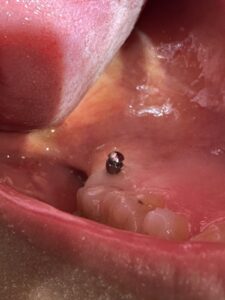

インプラントアンカーを入れている所

実際に入った所

入った後にCTで確認中

📸 写真でもわかるように、

ミスのないよう真剣な表情で取り組んでいます💡